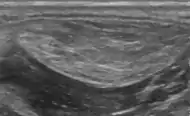

Medical ultrasonography of a lipoma in the thenar eminence: It is hyperechoic compared to adjacent muscle, and relatively well-defined, with miniature hyperechoic lines.[23]

A physical exam is typically the easiest way to diagnose it. Rarely, a tissue biopsy or imaging may be required. The imaging modality of choice is magnetic resonance imaging (MRI) because it has superior sensitivity of distinguishing it from liposarcoma as well as mapping the surrounding anatomy.[22]